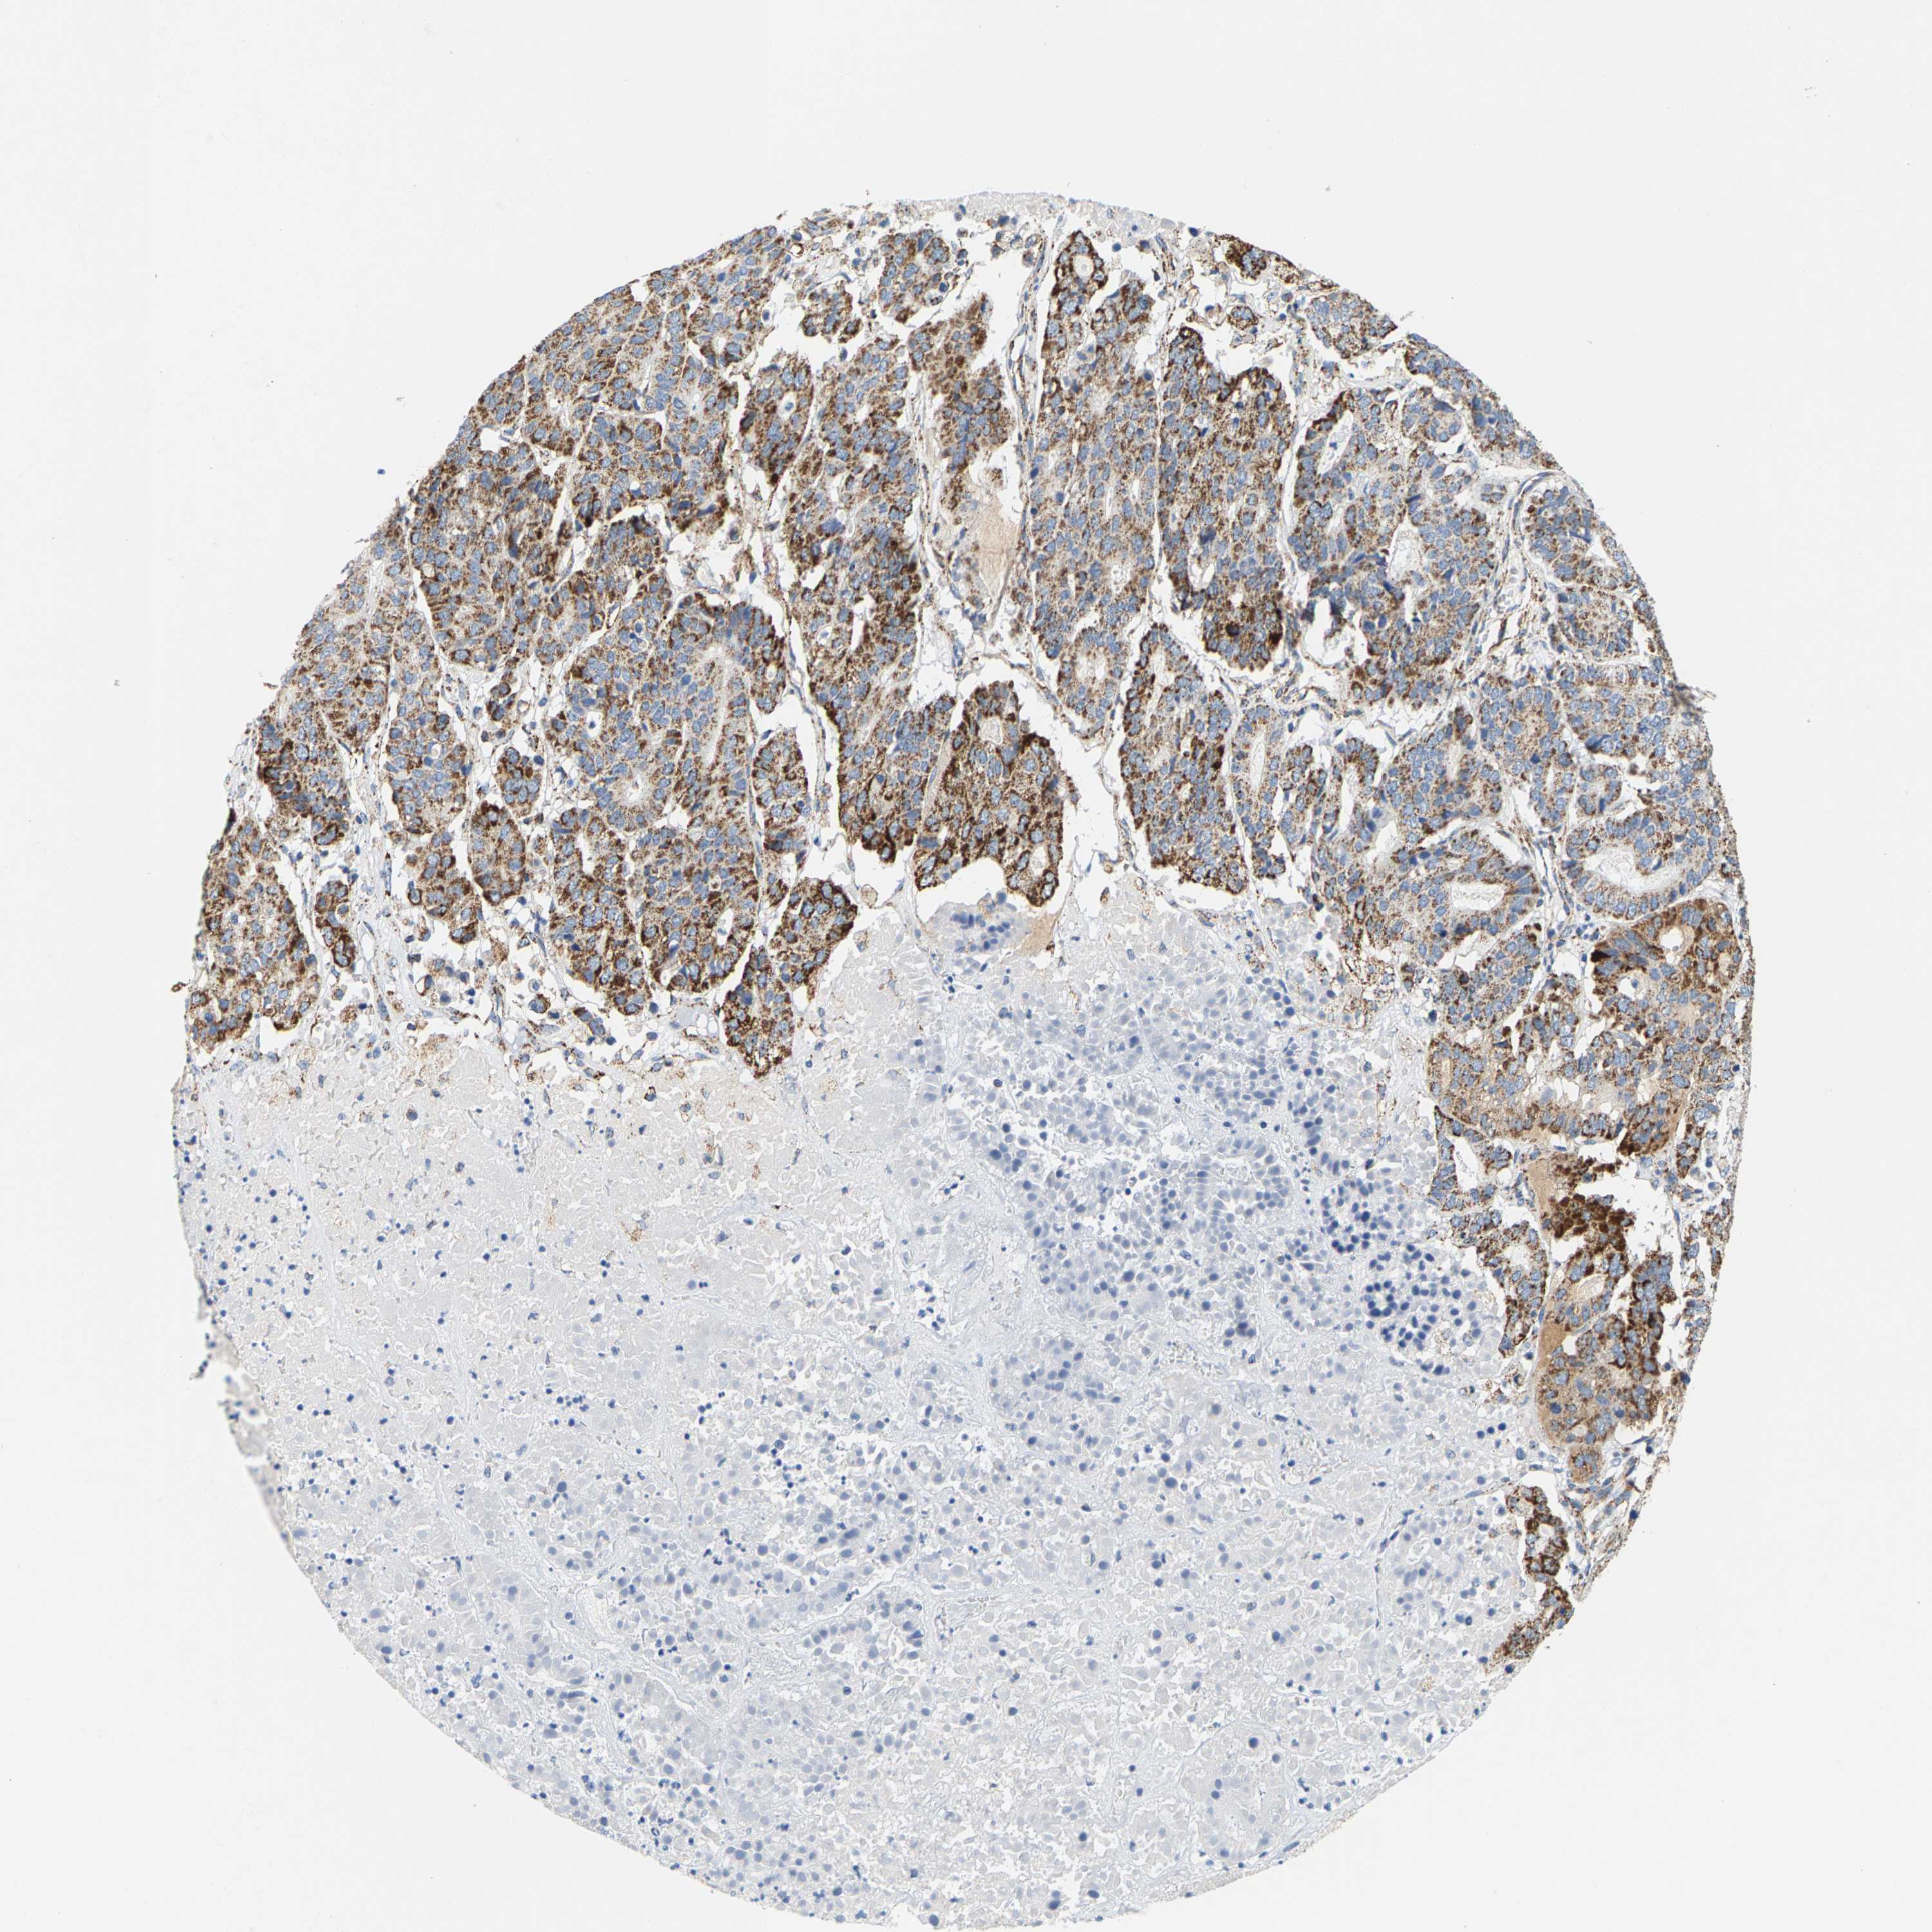

PANCREATIC CANCER - Protein expressioni

A mouse-over function shows sample information and annotation data. Click on an image to view it in a full screen mode. Samples can be filtered based on level of antibody staining by selecting one or several of the following categories: high, medium, low and not detected. The assay and annotation is described here.

Note that samples used for immunohistochemistry by the Human Protein Atlas do not correspond to samples in the TCGA dataset.

Antibody stainingi

Antibody staining in the annotated cell types in the current human tissue is reported as not detected, low, medium, or high, based on conventional immunohistochemistry profiling in selected tissues. This score is based on the combination of the staining intensity and fraction of stained cells.

Each image is clickable and will lead to virtual microscopy that enables deeper exploration of all samples and also displays staining intensity scores, fraction scores and subcellular localization as well as patient and tissue information for each sample.

Antibody HPA020543

Antibody HPA020549

Staining

High

Medium

Low

Not detected

Intensity

Strong

Moderate

Weak

Negative

Quantity

>75%

75%-25%

<25%

None

Location

Nuclear

Cytoplasmic/membranous

Cytoplasmic/membranous,nuclear

Adenocarcinoma, NOS